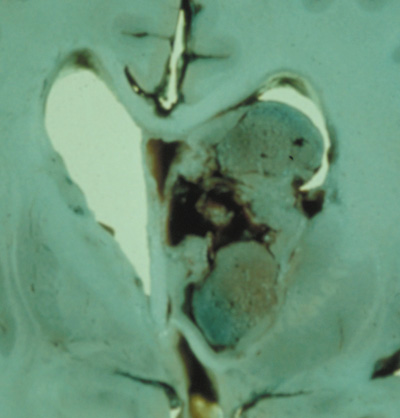

PANCREAS. Pancreatic lesions may be nonsecretory (most commonly cysts or cystadenomas) or secretory (islet cell tumor).179 In one study of 52 patients, 56% (29 patients) were found to have pancreatic lesions. The majority (19 of 29) had cystic changes only (Fig. 17C). Pancreatic lesions were the only abdominal manifestation of disease in 6 of 52 patients.180 In a separate study, pancreatic cysts did not show significant progression on follow-up examinations over an average period of 5 years.181 Like pancreatic cysts, islet cell tumors appear to be frequently asymptomatic.182 EPIDIDYMIS AND BROAD LIGAMENT. Papillary cystadenomas of the epididymis are typically benign and asymptomatic. In one study, about half of patients were affected.183 Papillary cystadenomas of the broad ligament are thought to be the female equivalent of papillary cystadenomas of the epididymis.184 OPHTHALMIC FEATURES VHL syndrome does not appear to have significant anterior segment manifestations. Posterior Segment Retinal capillary hemangiomas are among the most frequent and earliest manifestations of VHL syndrome. Most patients present between 10 and 40 (mean age of 25) years of age and 5% present before age 10. Overall, retinal capillary hemangiomas affect about 60% of individuals with VHL syndrome. Development of new retinal capillary hemangiomas after age 60 years is unusual.169,170 Retinal capillary hemangiomas (Fig. 18) may be the only manifestation of the syndrome,185 and typically involve the midperipheral temporal retina.186 A pair of dilated and tortuous retinal vessels (artery and vein) classically supply the vascular tumor. Without fluorescein angiography, it may be difficult to distinguish artery from vein on fundus examination.170

Retinal capillary hemangiomas may also occur in the absence of VHL syndrome, but the age at presentation is typically later (50 vs. 25 years).187 Small retinal capillary hemangiomas may remain stable for many years, but most tend to enlarge and may become symptomatic secondary to exudation and retinal detachment. On microscopy, retinal capillary hemangiomas are similar in appearance to the CNS hemangiomas of VHL syndrome. Thin vascular channels are lined by endothelial cells and pericytes. The vascular channels are separated by foamy stromal cells. The foamy appearance is due to phagocytosed lipids that escape the fenestrated endothelium of the vessel walls. The lipid is plasma–derived cholesterol stearate.188–190 Hemangioma is more appropriate than hemangioblastoma.170,188,190 The cellular origin of capillary hemangiomas in VHL is controversial,170 but loss of heterozygosity of the VHL gene has been demonstrated in the stromal cells of capillary hemangiomas.191 There are various classification schemes based on morphology (endophytic, exophytic, and sessile) and the presence or absence of exudation. Endophytic tumors grow on the retinal surface, protruding into the vitreous cavity. Exophytic tumors tend to be nodular and orange-colored, growing the in outer layers of the retina. The sessile growth pattern implies a flat tumor, gray or orange in color, and grows within the middle layers of the retina.185 The “natural history” of the retinal capillary hemangioma has been divided into four192 or five193 stages170: